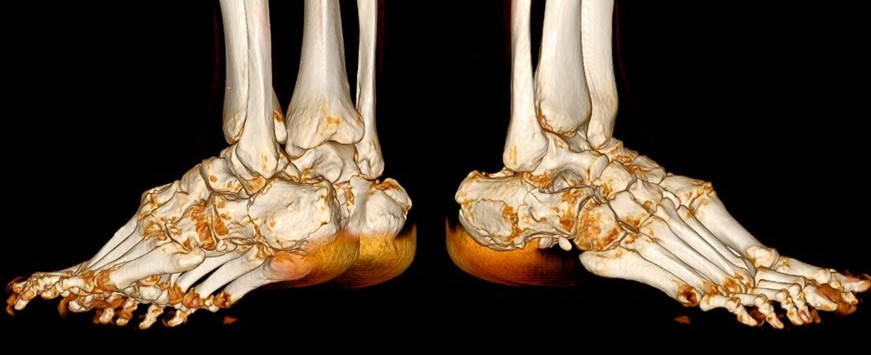

Лікар-травматолог — це детектив, що розгадує загадку травми. Кожна деталь має значення: як сталося падіння, з якої висоти, на яку поверхню. Механізм травми розповідає таємниці майбутніх ускладнень — падіння з висоти шепоче про можливі двосторонні переломи п’яткових кісток, пошкодження таранної кістки та компресію хребців, аварія у ДТП кричить про поєднані травми.

Але рентген — лише силует, тінь реальності. Справжню карту руйнувань малює комп’ютерна томографія (КТ) — безжальний картограф, що шар за шаром зрізає тканини, показуючи перелом у всій його тривимірній жорстокості. Тут видно кожен уламок, кожну тріщину, кожне зміщення. КТ дозволяє побачити те, що приховане від звичайного погляду — як суглобова поверхня розламана на шматки, наче дзеркало, що впало на підлогу.

Перелом обох пʼяткових кісток одночасно — це подвійне випробування, подвійний час нерухомості, подвійна втрата функції.